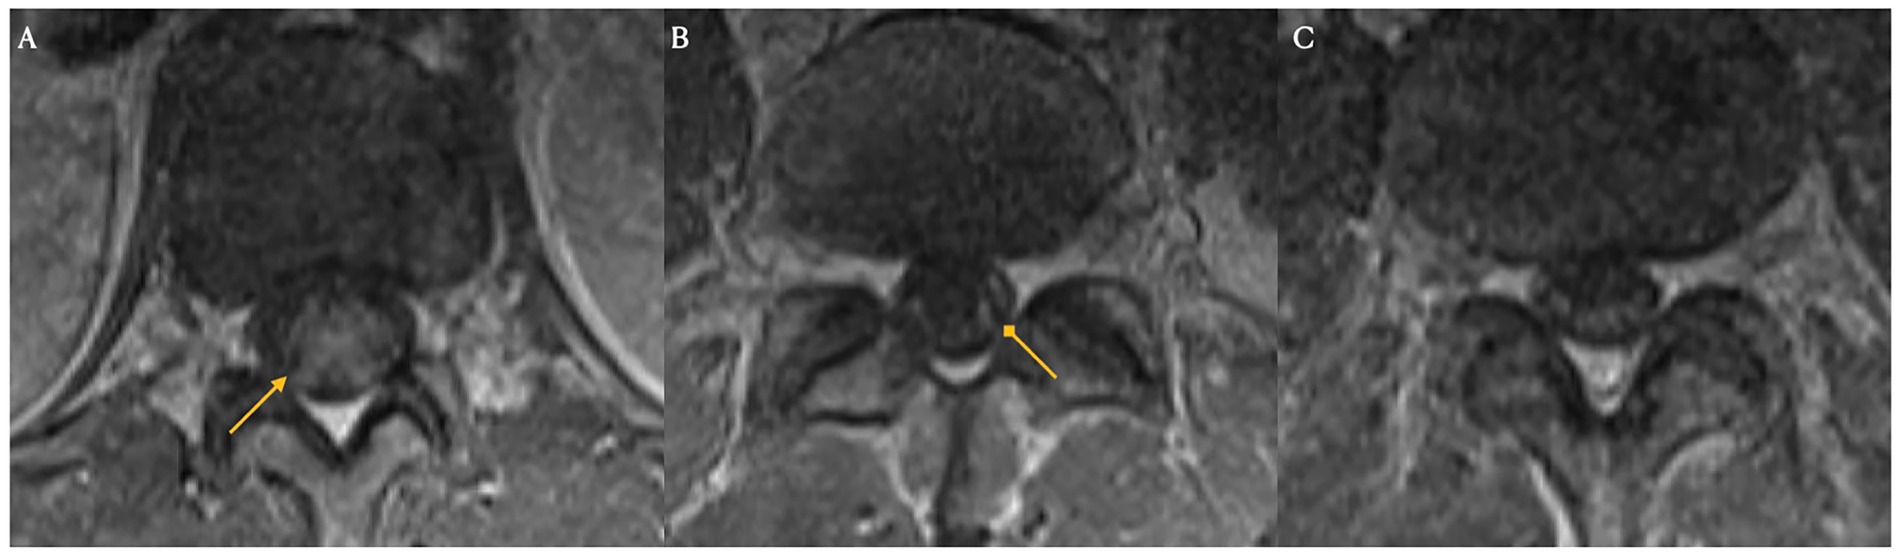

The clinical timeline for this patient is illustrated in Figure 2. One day after CAR T-cell therapy, the patient developed persistent fevers consistent with grade 1 CRS, and was treated with tocilizumab, resulting in resolution of the fever. However, 3 days later, he experienced recurrent grade 1 CRS with fever and grade 1 immune effector cell-associated neurotoxicity syndrome. The patient’s condition rapidly deteriorated, progressing to grade 3 ICANS (aphasia) and subsequently to grade 4 ICANS, characterized by seizure activity. On day five, he was intubated for airway protection and transferred to the intensive care unit (ICU). MRI of the brain revealed diffuse leptomeningeal enhancement, widespread T2 and FLAIR hyperintensities throughout the cortex and pons (Figure 3), and focal FLAIR hyperintensity in the left mesial temporal lobe (Figure 4), potentially related to recent seizure activity. These neuroimaging findings were consistent with ICANS-associated changes. The patient was started on dexamethasone and anakinra for the management of ICANS-related neurotoxicity, and by the following day, there was a marked reduction in leptomeningeal enhancement.

Figure 4

Three MRI brain images are shown. Image A and B are from Day 4, with arrows pointing to highlighted areas, indicating possible abnormalities. Image C from Day 21 shows a brain scan without annotations, suggesting a change over time.

Figure 4. Brain magnetic resonance imaging on days four and 21 post-CAR T-cell infusion. ICANS-associated brain MRI findings showing focal FLAIR hyperintensity in the left mesial temporal lobe (Panels A,B), which may reflect recent seizure activity. Images from pre-treatment (Day 4: Panels A,B) and post-treatment (Day 21: Panel C) with steroids and Anakinra demonstrate resolution of the lesion.

Both the present case and the case described by Koch et al. developed immune effector cell associated neurotoxicity syndrome. In the Koch et al. case, the patient exhibited simultaneous onset of grade 2 ICANS (disorientation) and GBS-like symptoms on day five, with no ICANS related findings on brain MRI. In contrast, our patient developed grade 1 ICANS on day three, which progressed to grade 3 (aphasia) and grade 4 (seizures) by day four. Brain MRI in our presented case revealed imaging features typical of ICANS, including leptomeningeal enhancement and diffuse T2/FLAIR hyperintensities in the cortex and pons. These findings resolved with treatment using dexamethasone and anakinra. However, following extubation on day nine, the patient developed new-onset neurological deficits and spinal MRI findings consistent with Guillain-Barré syndrome following apparent resolution of ICANS.